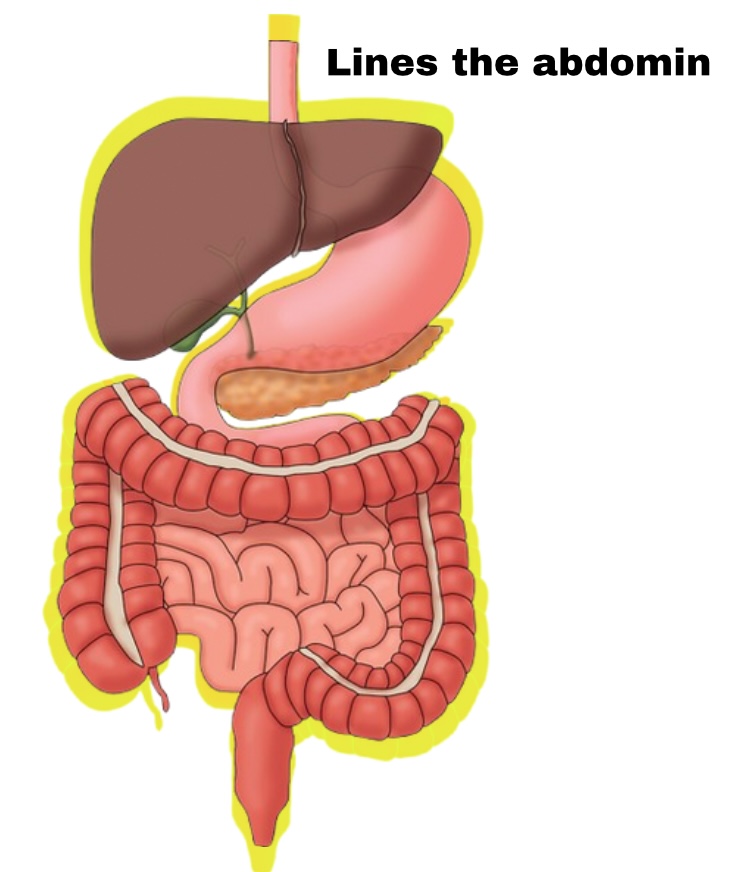

Peritoneum

Membrane lining abdomen

Partial Peritoneum

Outer layer

Visceral Peritoneum

Deep layer (surface of organ)